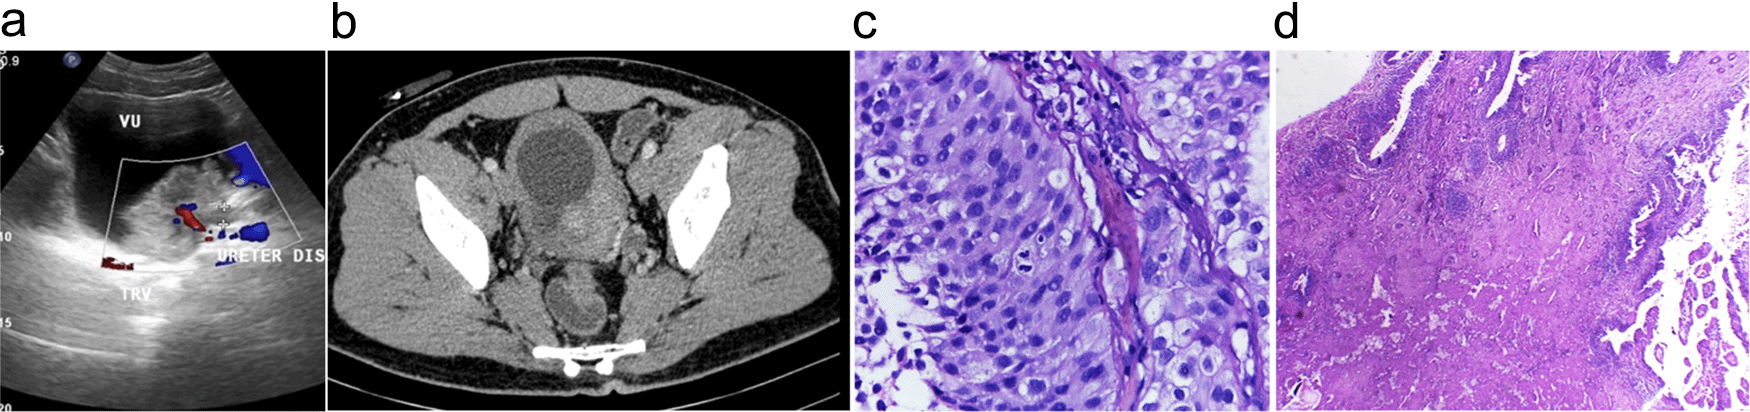

The patient was an active smoker for 20 years and ate roasted meat regularly. From ultrasound and contrast computed tomography (CT) scan evaluation, a mass was discovered in the bladder (Figure 2a). A cystoscopy and an incomplete transurethral resection of bladder tumour (TURBT) was then conducted on the papillary mass in the bladder. Furthermore, a biopsy was conducted, and pathology examination concluded that the tumor was an infiltrative papillar urothelial carcinoma pT1 high grade (Figure 2b). In March 2018, the patient had bilateral hydronephrosis, and bilateral nephrostomy was confirmed. The bladder UCC was clinically diagnosed as cT2N0M1, and the patient was given 6-cycle neoadjuvant gemcitabine-cisplatin chemotherapy. During the chemotherapy phase, the patient was in good condition with a Karnofsky score of 90. In July 2018, a radical cystectomy followed by an orthotopic neobladder was conducted. Meanwhile, the frozen section of the right and left ureter, and urethral punctum showed no tumor. Pathology examination showed chronic inflammation of hyperplastic urothelium, with fibrinoid necrosis (Figure 2c).

(a) Contrast computed tomography (CT) scan in December 2019 showing isodens mass that enhanced after contrast administration in the bladder. (b) Ultrasound in March 2020. An isoechoic lesion with irregular edges, on the left inferolateral bladder wall, and appears to be obstructing the left ureter with its distal part dilated. (c) The initial diagnosis was infiltrative high-grade urothelial carcinoma. The pictures show tumor cells with round/oval nuclei, pleomorphic, coarse chromatin, vesicular with nuclei, Hematoxylin and Eosin (H&E) stain 400×. (d) A follow-up biopsy showing urethra with minimal inflammatory infiltration. The picture showed that no tumor was found, chronic inflammatory, fibrinoid necrosis, H&E stain 100×.